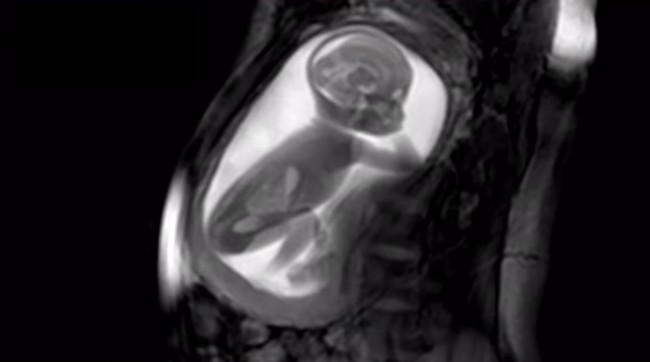

Desde hace unos años, al llegar la alta definición a los ecógrafos, la interpretación es más simple; aunque sí es verdad que hay momentos en que sigue siendo complicado saber qué estamos viendo. Pues bien, es probable que esta sensación de los padres llegue a su fin, si las ecografías por resonancia magnética se extienden y llegan a ser de uso habitual. Las diferencias son bastante evidentes: un vídeo muestra cómo serán las 'ecografías' en el futuro.

Creado en Londres con un presupuesto de 10 millones de libras, el proyecto iFind tiene como misión lograr la tecnología necesaria para poder hacer ecografías rutinarias mediante tecnología magnética y ondas de radio.

A la vista de lo que se puede apreciar en este vídeo, lo han conseguido:

El material que consiguen es tan detallado que se puede ver al bebé girando el cuello, jugando con el cordón, saltando, encongiéndose, etc. En el caso del vídeo, el feto tiene 20 semanas de vida y por eso se le ve el cuerpo entero.

Y esto es lo más increíble: mediante unos algoritmos, el ecógrafo es capaz de captar la imagen de todo el útero e incluso el cuerpo de la madre, en alta calidad. Nada de ver un brazo, ahora una pierna, ahora la cabeza, ahora "no sé qué es esto", etc. En una sola imagen se ve al bebé por completo, de manera que se puede tener una idea muy clara de lo que está haciendo en cada momento.